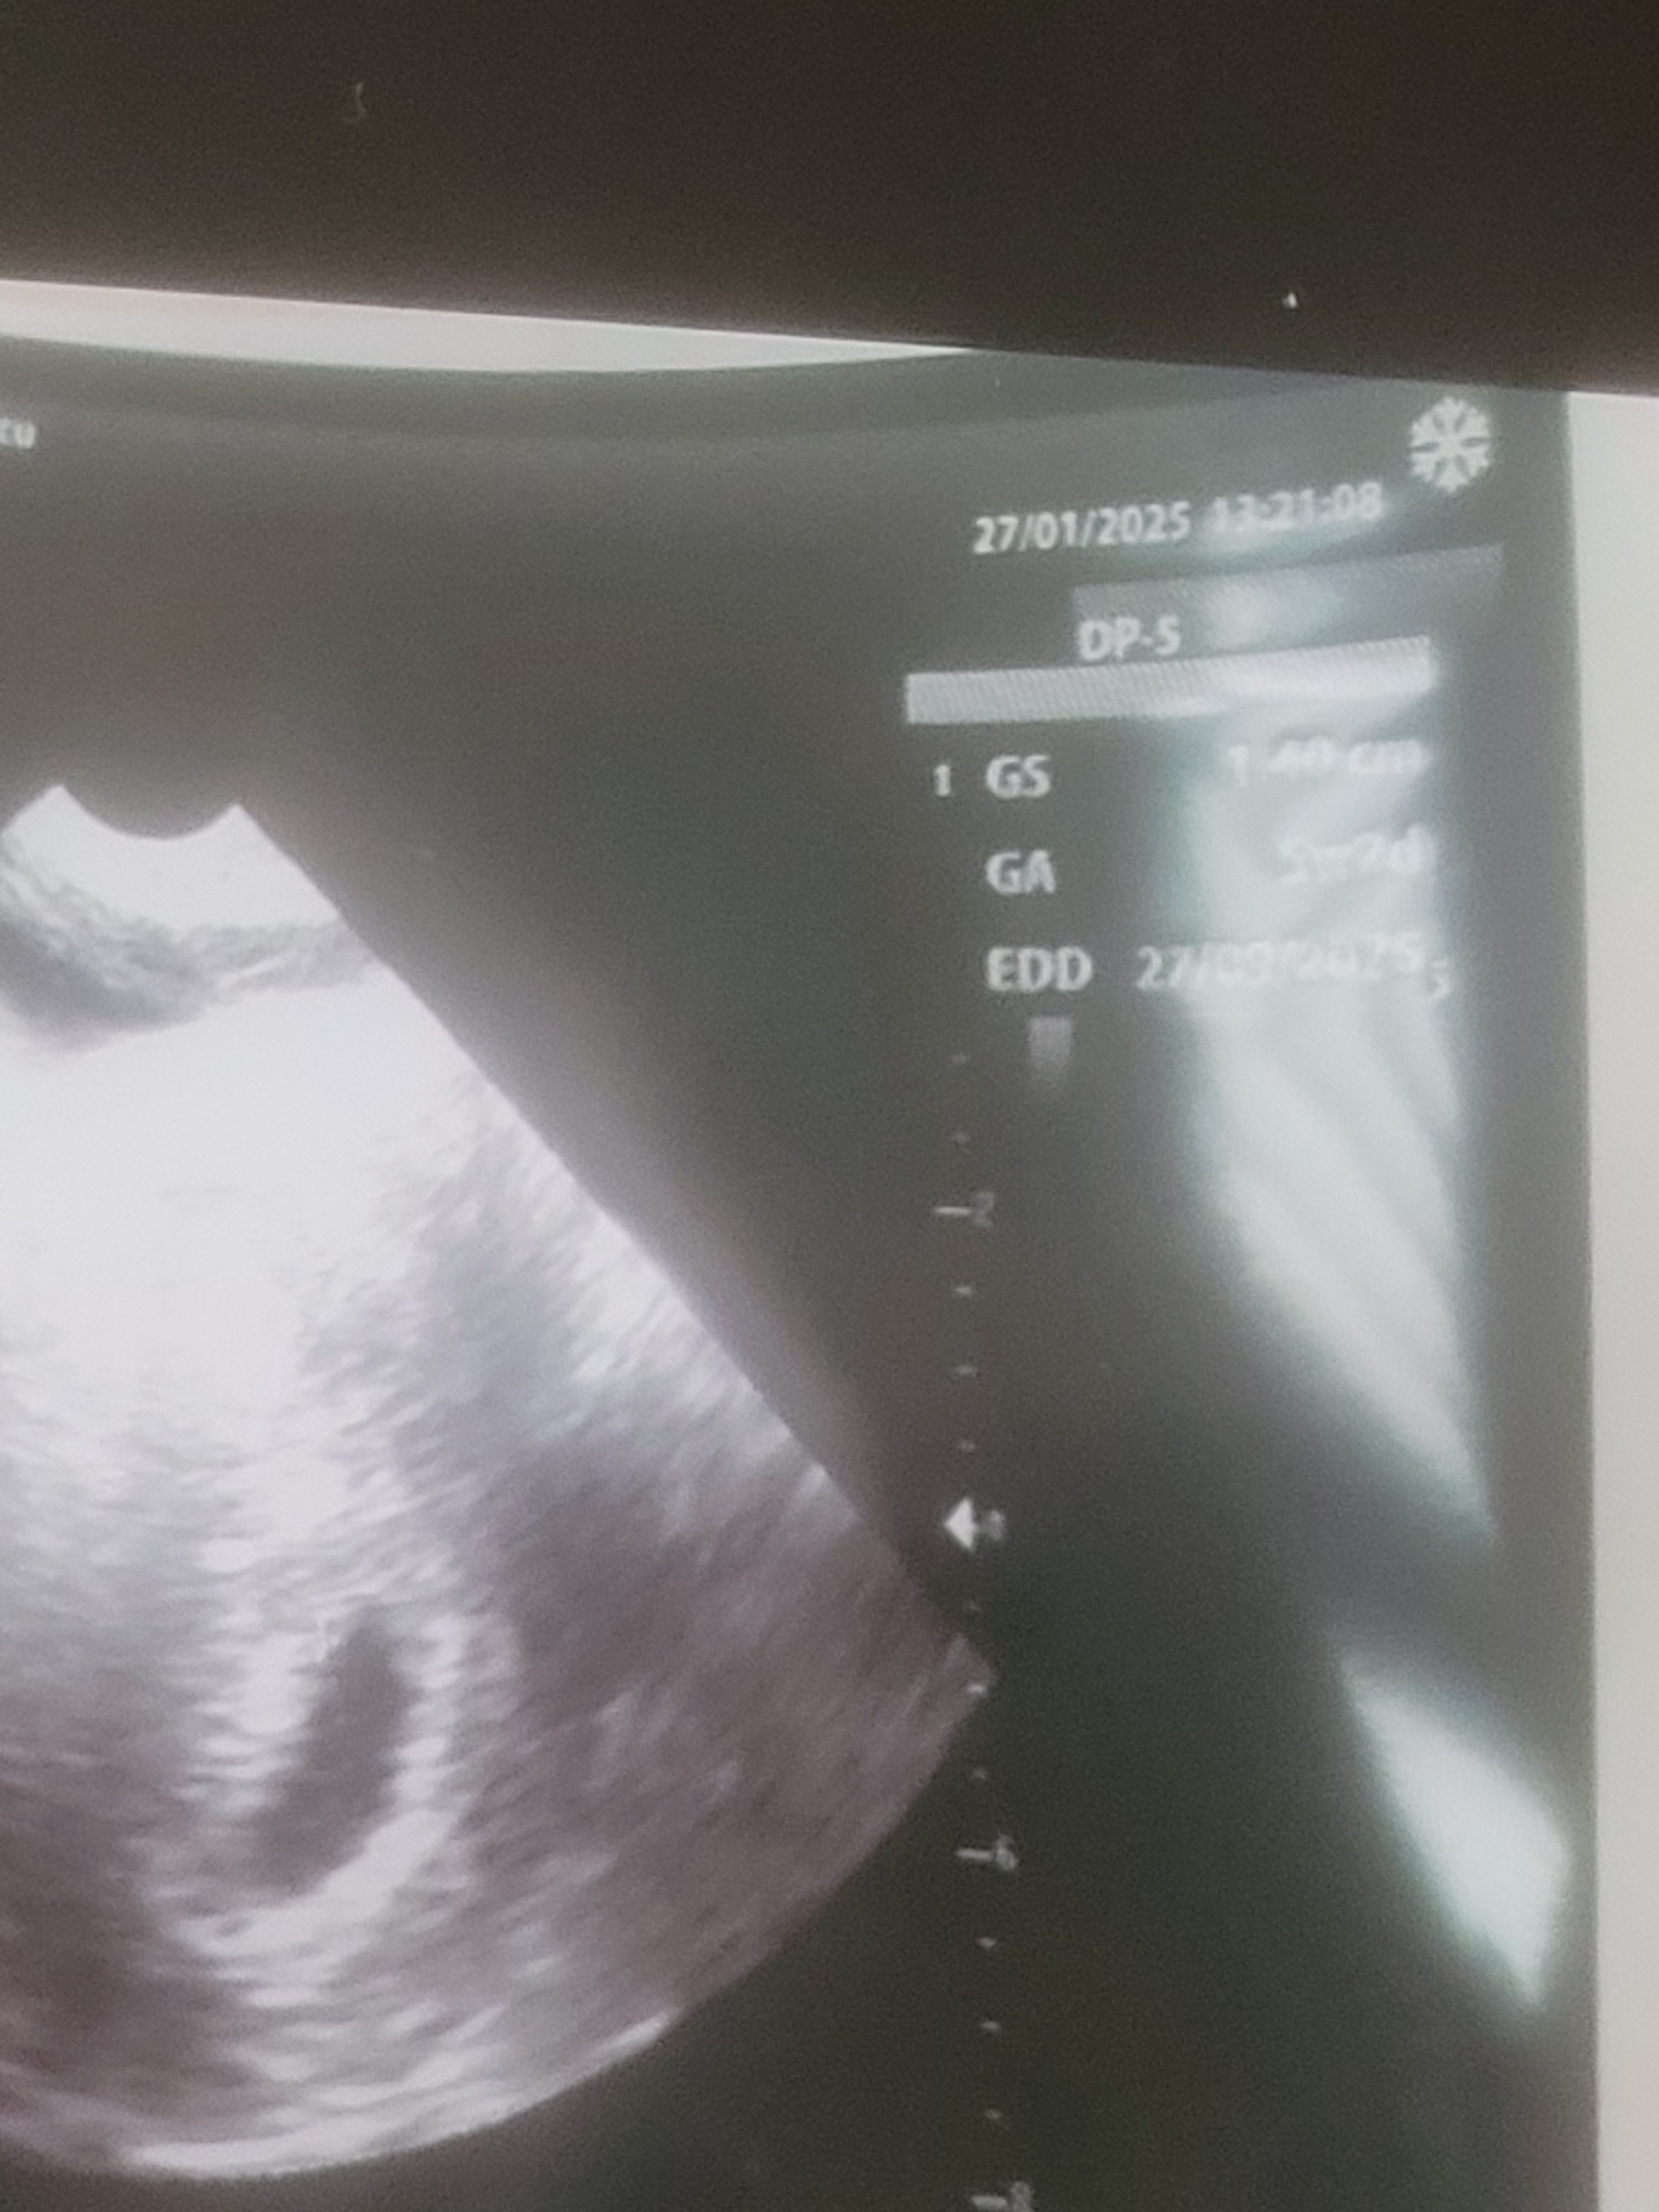

Zobacz załącznik 1685141

Piszę 5 tc 2 dni.... martwię się czy zarodek się pojawi a nie kiedy zaszlam

Byłaś na USG 16.01 i pęcherzyk wskazywał na 4t6d, a dzisiaj po 11 dniach masz 5t2d

To jest zdecydowanie za mały przyrost. Wręcz jego brak - GS z 0.98 na 1.4 (pęcherzyk ciążowy powinien rosnąć min. 1mm na dobę)

W teorii pęcherzyk żółtkowy powinien pojawić się przy pęcherzyku max. 10mm i zaraz potem zarodek. Jeżeli pęcherzyk ma powyżej 25mm i nie ma pęcherzyka żółtkowego, ani zarodka to mówimy o pustym jaju płodowym

Na szczęście ma 1.40mm więc jeszcze tydzień do następnej wizyty chyba nie jest przesądzony